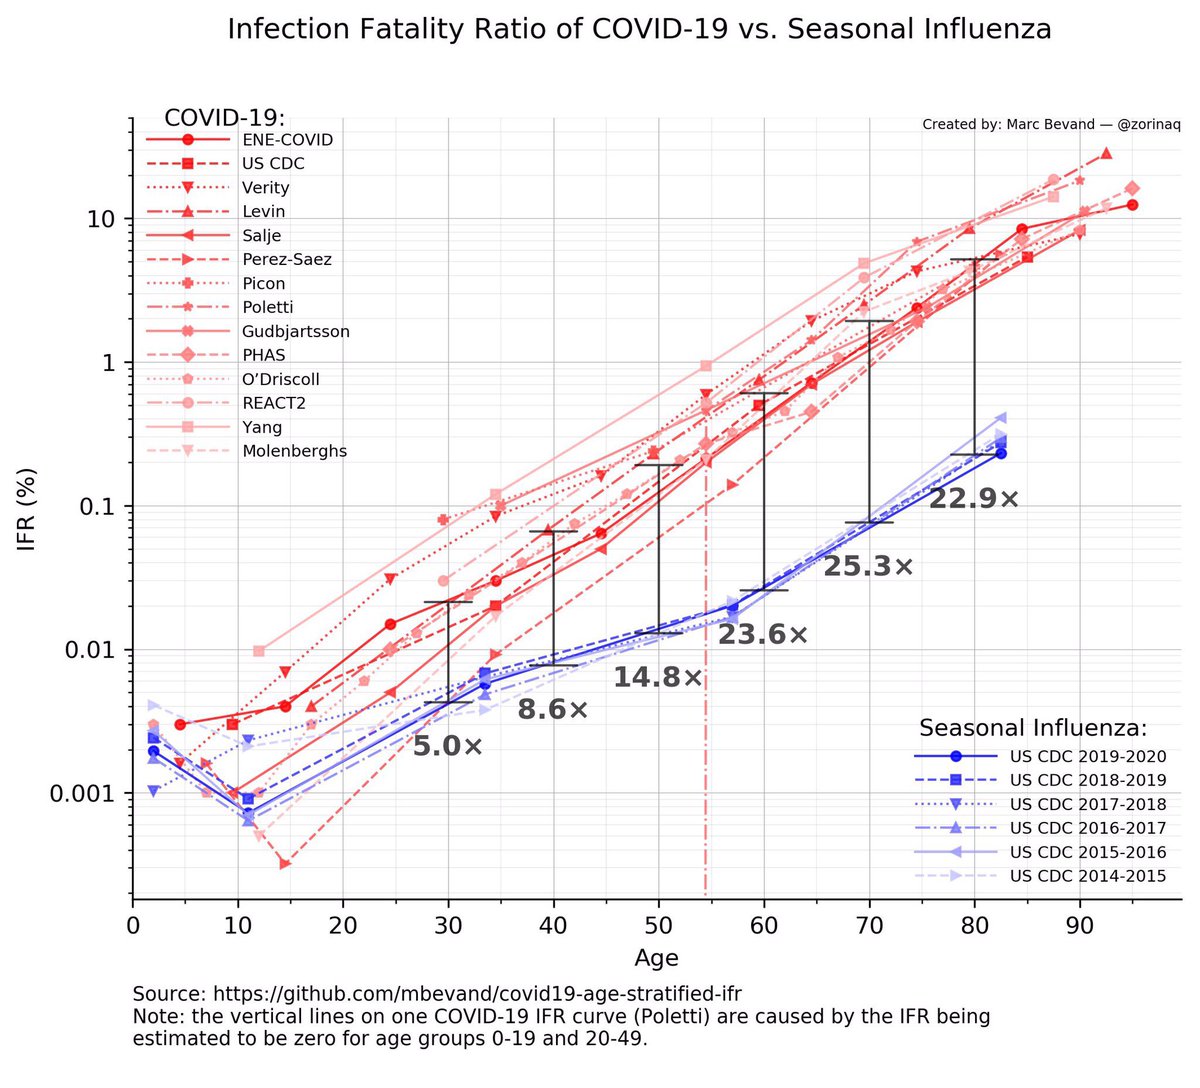

6/ At 33 my risk of during from COVID is 5x higher than dying from flu.

When I get to my 80s it’s 25x higher.

This is not flu.

HT @zorinaq

When I get to my 80s it’s 25x higher.

This is not flu.

HT @zorinaq